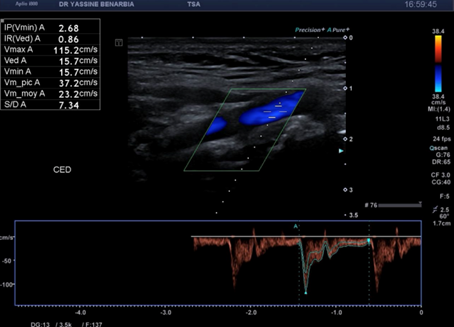

Du côté droit, l'examen met en évidence une dissection du tronc brachiocéphalique (TABC) avec présence d'un faux chenal circulant. Le flap intimal est clairement visible en mode B, séparant le vrai chenal du faux chenal. Au Doppler couleur, on observe un double flux avec des vélocités différenciées : le vrai chenal présente un flux rapide (codé en bleu qui s’éloigne de la sonde) tandis que le faux chenal montre un flux plus lent (codé en rouge qui se rapproche de la sonde).

Cette dissection s'étend à la carotide commune droite proximale. Le Doppler pulsé dans le vrai chenal montre un spectre triphasique conservé avec une vélocité maximale de 108,0 cm/s (normale) et un index de résistivité de 0,84 confirmant l'absence de retentissement hémodynamique. L'artère sous-clavière droite et l’artère vertébrale restent perméables avec des flux normaux au doppler.